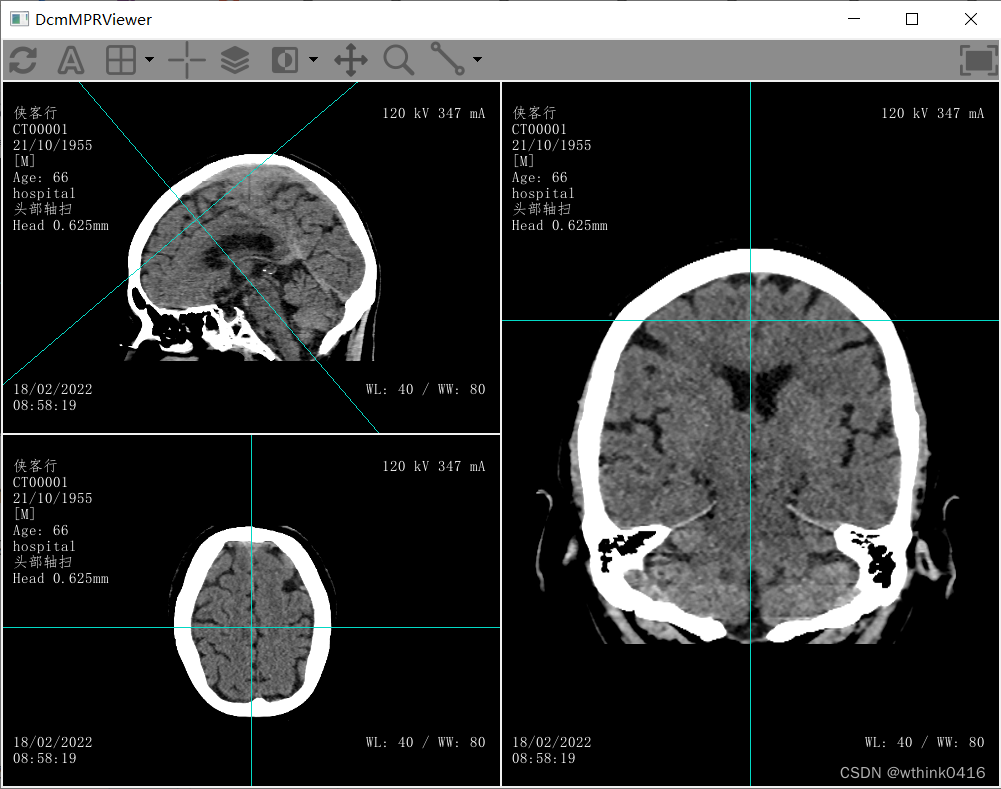

20、选中分割线,同时鼠标左键移动可以实现分割平面的旋转,或者选中分割线的焦点,同时鼠标左键移动可以调整分割平面的中心位置